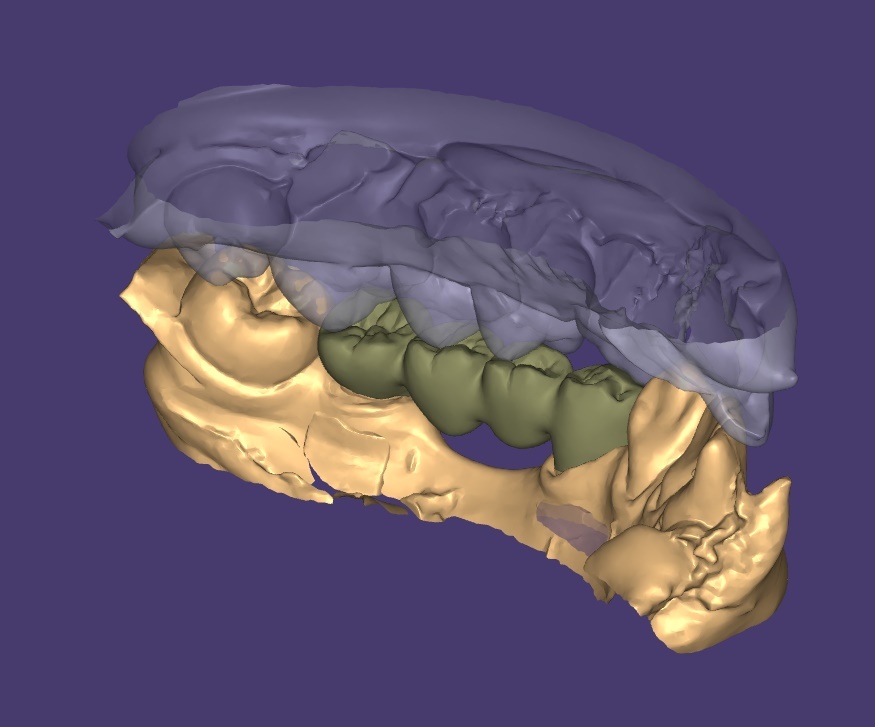

그래서 선택한 방법은 컴퓨터 디자인 기반의 정밀 치료 계획이었습니다.

컴퓨터 디자인을 통해 환자의 구강 구조를 3D로 분석했습니다.

- 턱관절의 움직임 패턴

- 현재 쏠린 치아들의 각도

- 교합 평면의 기울어진 정도

모든 데이터를 수치화하고 시뮬레이션했습니다.

"단순히 치아를 심는 것이 아니라, 무너진 균형을 다시 세우는 작업이었습니다."